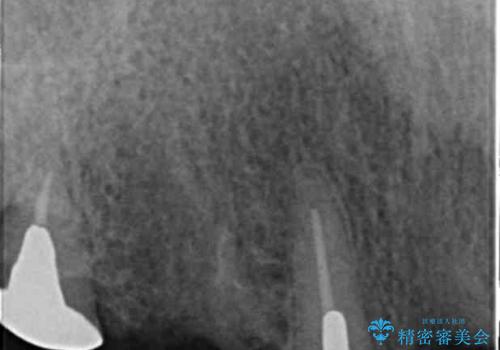

- 交通事故により前歯が折れたことを主訴に来院された患者様です。

精査したところ、前歯以外にも歯が折れており、上の歯の多くが保存不可能な状態でした。

保存可能な2本の歯を用いて、マグネットデンチャー(磁性アタッチメントを用いた入れ歯)による治療を行いました。